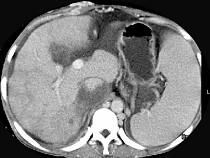

问题 女性,26岁,腹胀不适7月,腹软,肝右肋缘下1cm,影像检查如图,可能的诊断为 ( )

选项 A.肝血管瘤 B.原发性肝癌 C.肝硬化腹水 D.巴-希综合征 E.脂肪肝

答案 D